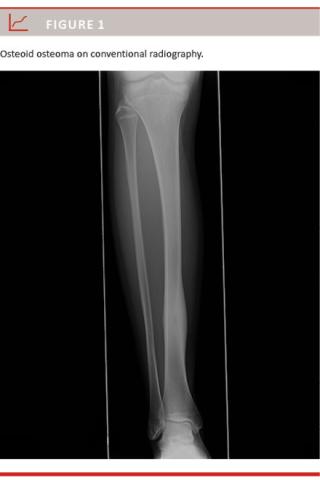

rounded by reactive bone sclerosis (Figure 1). The diagnosis may also be established by computed tomography (CT) where the characteristic appearance of OO is a low-attenuation nidus with a varying amount of bone sclerosis (Figure 2). Occasionally magnetic resonance imaging (MRI) and rarely bone scintigraphy are preformed to confirm the diagnosis [4, 6]. Bone scintigraphy is made with Tc-99-labelled diphosphonates, which accumulate in areas with increased osteoblastic activity and bone turnover and therefore have a markedly increased uptake in the nidus [4].